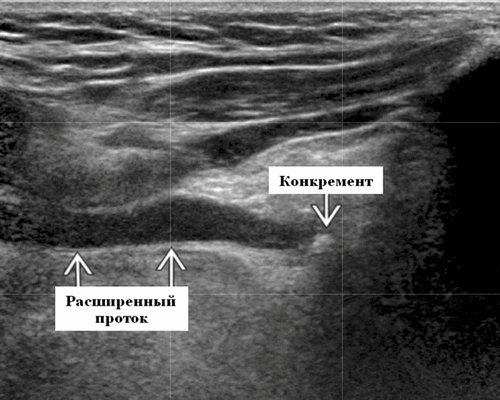

- Острый калькулезный сиаладенит (ОКС). Односторонняя, увеличенная, гипоэхогенная, гетерогенная поднижнечелюстная железа (ПЧЖ). Расширение интра- / внегландулярных протоков и слюнной камень. Болезненность при давлении датчиком, нет явного повышения васкуляризации при ЦДК

- Всегда необходимо отслеживать всю длину протока слюнной железы (СЖ) на УЗИ в нескольких плоскостях и сравнивать с противоположной стороной.

- Увеличенный проток СЖ часто является лучшим признаком наличия камня / стеноза.

Место расположения. Поднижнечелюстное пространство (ПНП); Камни ПЧЖ можно разделить по местоположению. Дистальный: к отверстию протока в переднем подъязычном пространстве (ППП). Проксимальный: В сторону ворот поднижнечелюстной железы в подчелюстном пространстве. Камни поднижнечелюстной слюнной железы на УЗИ чаще встречаются в протоке, чем в ее паренхиме.

Острый калькулезный сиаладенит. Одностороннее поражение, увеличенная, гипоэхогенная, неоднородная структура железы на УЗИ. Расширение интра- / внегландулярных протоков и слюнной камень. Нет явного увеличения кровоснабжения. Болевая реакция при надавливании датчиком на зону воспаления

Рекомендации по визуализации. Лучший инструмент для диагностики - проведение УЗИ. Это идеальный метод визуализации для сиаладенита ПЧЖ, поскольку он полностью оценивает структуру железы и выявляет конкремент, расширение протока и осложнения (например, образование абсцесса). Для обнаружения слюнных камней чувствительность УЗИ составляет 77%, а специфичность - 95%. Ложноотрицательный результат возникает из-за небольшого размера камня Что важно при проведении ультразвукового сканирования? Обязательно использование датчика с высоким разрешением (≥ 7,5 МГц). Всегда отслеживайте всю длину главного протока ПЧЖ в нескольких плоскостях и сравнивайте с противоположной стороной. Увеличенный Вартонов проток часто является лучшим признаком наличия камня или его стеноза. Оцените соседние лимфоузлы, так как они могут увеличиваться во время острого приступа заболевания.